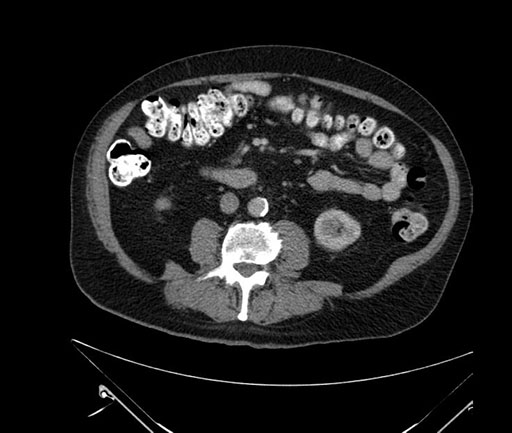

Axial - stented